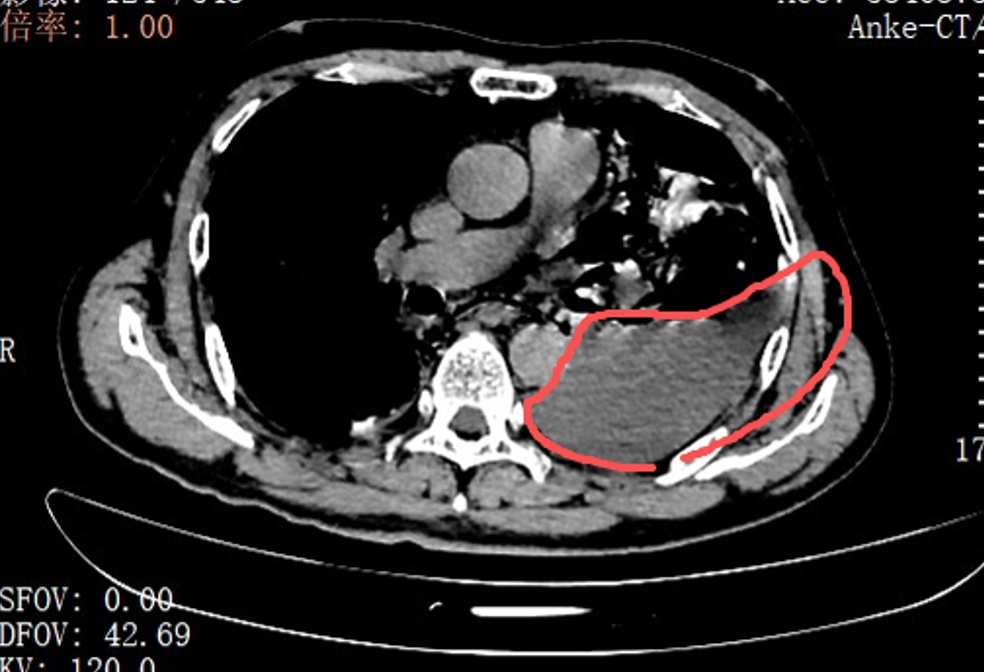

红圈区域是食物残渣、消化液破入食管

手术团队拿着吸引器,一点点清理、冲洗,花了很长时间才将胸腔里的每一点食物残渣都清干净。随后,团队找到了食道下段那道长达10公分的裂口,用可吸收线小心翼翼地完成了分层修补。